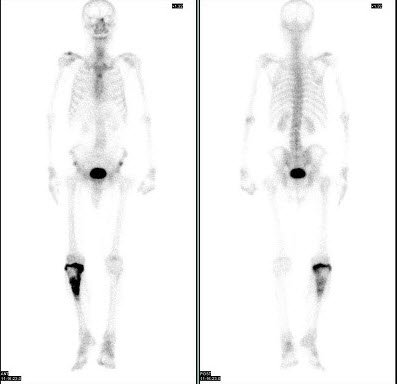

3、多项选择题

男,36岁,诉晨起酸痛数月,行99Tcm-MDP骨显像如图,对此影像描述正确的是()

A.提示多发骨转移

B.提示肺性肥大性骨关节病

C.是超级骨显像

D.颅骨散在圆点状浓聚提示病理过程的出现

E.提示多发性骨髓瘤